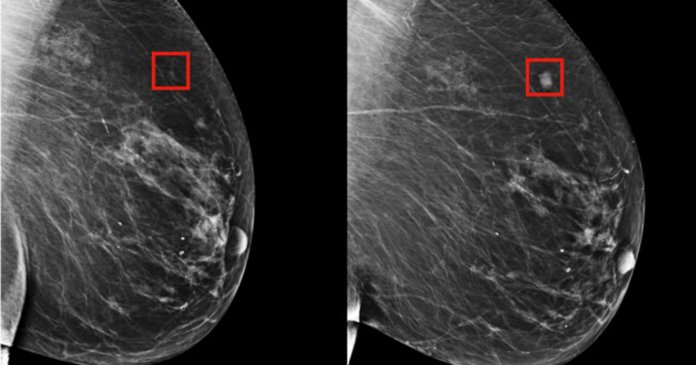

A tecnologia foi testada com dados de 2009 a 2012, provenientes de 90 mil mamografias de mais de 6 mil pacientes do Massachusetts General Hospital. Com a ajuda do sistema de inteligência artificial, foram detectados padrões sutis que não podiam ser identificados por humanos nos tecidos mamários, conseguindo antever as chances do desenvolvimento do câncer.

A inteligência artificial desenvolvida pelos pesquisadores previu 31% dos casos de pacientes de alto risco, o que representa uma melhora considerável na prevenção da doença, uma vez que as técnicas tradicionais anteriores podiam prever apenas 18% desses casos. Os métodos anteriores foram criados com base em dados de mulheres brancas, e um estudo publicado no Journal of Women’s Health mostrou que a eficácia dos testes de prevenção deixava de lado a população negra e hispânica.

Por outro lado, agora o modelo criado pela IA foi testado também em mulheres negras, podendo ser mais acessível, embora os testes ainda precisem ser feitos em mulheres indianas e de outras etnias. A tecnologia permitiu ainda conhecer riscos individuais de cada paciente, informações que podem ser usadas para customizar programas de prevenção.